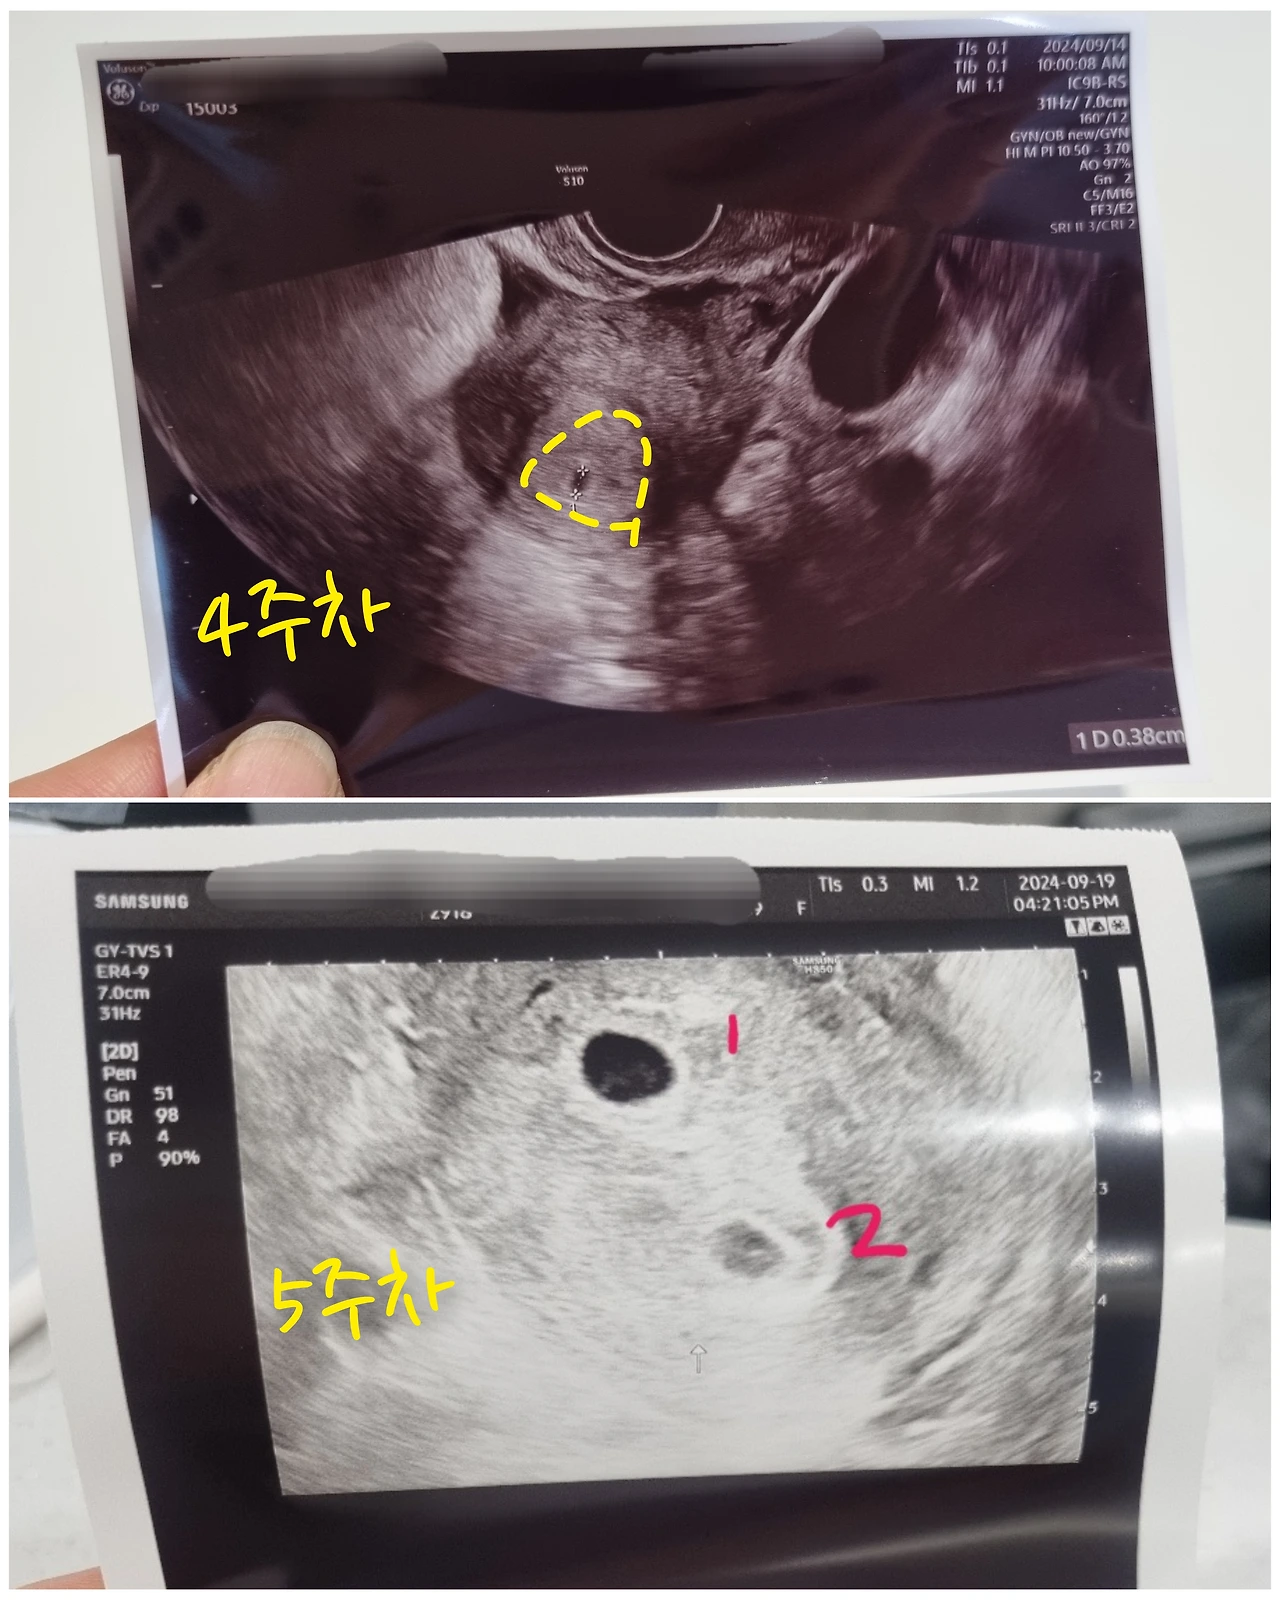

초음파 화면에는 지난주에 본 것보다 크기가 훨씬 커진 동그란 아기집 아래로 그보다는 살짝 작은 희미한 동그라미가 또 한 개 보였다.

'임신 4주 차에는 아기집이 1개였는데, 5주 차에는 2개가 되다니...! 정말 다이내믹한 9월이구나ㅎㅎ'